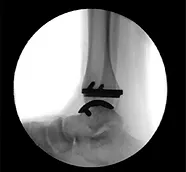

תמונת שיקוף לאחר איחוי קרסול